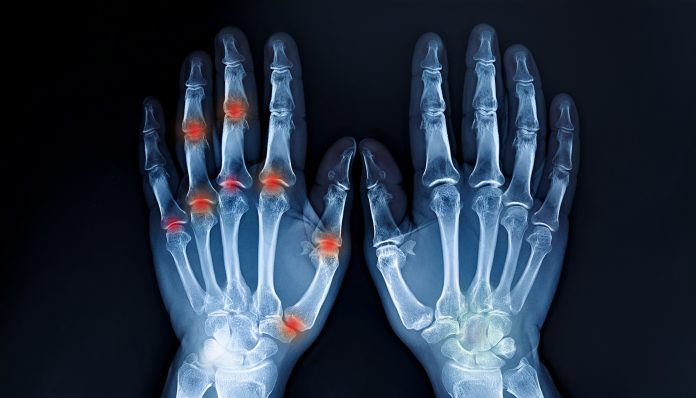

Prirodni Lijekovi za Ublažavanje Bolova u Zglobovima

U današnje vrijeme, sve više ljudi traži prirodne načine za liječenje zdravstvenih problema, posebno kada su u pitanju bolovi u zglobovima i reumatske tegobe. Suočeni s nuspojavama jakih lijekova, mnogi se okreću prirodnim lijekovima koji nude olakšanje bez štetnih efekata. Ovaj članak istražuje različite prirodne tretmane i savjete za ublažavanje bolova u zglobovima, uz primjere uspješnih iskustava i istraživanja koja podržavaju ove metode.